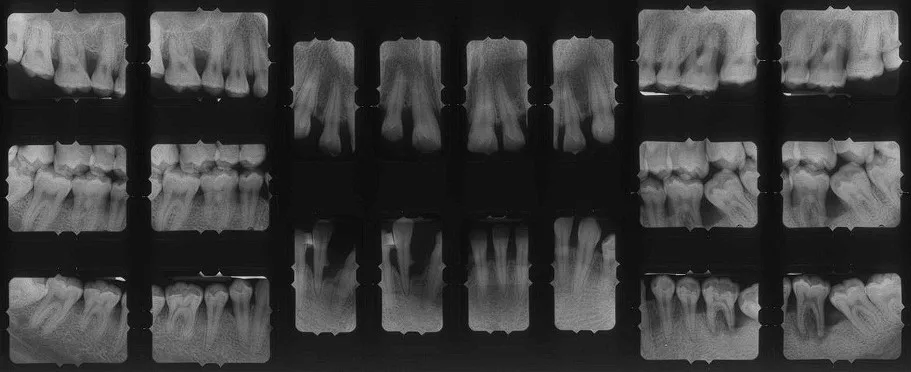

L’examen radiographique complète l’examen clinique.

L’examen de référence en parodontologie est le bilan long cône, constitué de radiographies rétro alvéolaires de toutes les dents réalisées à l’aide d’angulateurs. Les images obtenues ne sont ainsi pas déformées, contrairement à une radiographie panoramique qui ne peut constituer qu’un examen de débrouillage.